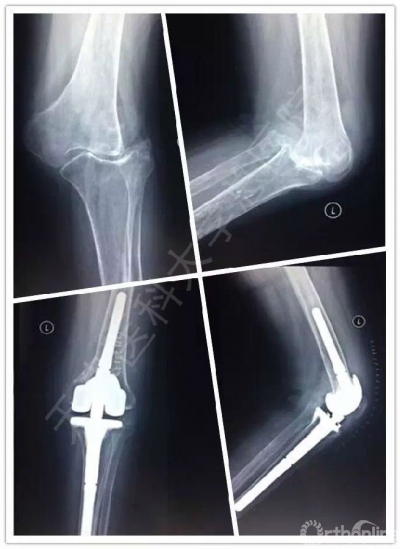

术前、术后关节X线对比

术前、术后关节侧位对比,术后关节屈曲畸形完全纠正,屈伸活动良好

左图:术前关节正位图,严重外翻畸形且屈伸活动受限

右图:术后关节正位图,关节畸形完全纠正且屈伸活动恢复正常